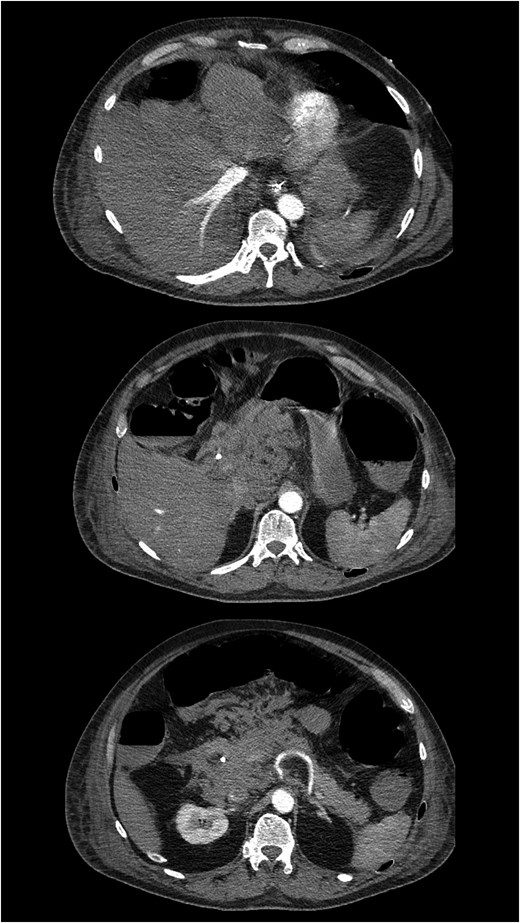

Unfortunately, during the ICU stay, the patient developed progressive shock, requiring mechanical ventilation and vasopressor therapy. Continuous veno-venous hemofiltration was initiated because of acute kidney failure. Repeat laboratory tests showed a hemoglobin level of 6.7 mmol/l, a C-reactive protein level of 213 mg/l, a white blood cell count of 24.9 × 109/l, and evidence of acute liver failure (total bilirubin 135 μmol/l, AST: 5720 U/l; ALT: 1620 U/l, prothrombin time: 1.9). Multiphase liver protocol CT demonstrated increasing retroperitoneal oedema with complete encasement of both arterial and portal vasculature, resulting in markedly reduced arterial liver perfusion (Fig. 1). An anatomical variant of the hepatic vasculature was noted, with the right hepatic artery arising from a small accessory branch of the coeliac trunk, and the left hepatic artery partially originating from the left gastric artery and partially from the gastroduodenal artery.

Contrast-enhanced CT demonstrating hemorrhage within the hepatoduodenal ligament and decreased arterial liver perfusion.